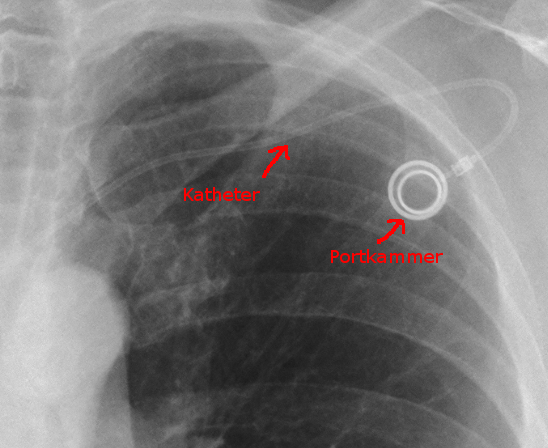

Das Bild links zeigt eine Röntgenaufnahme:

Portkatheter; implantiert im Bereich der oberen linken

Rippenbögen unterhalb des Schlüsselbeins.

Der Schlauch (Katheter) führt von der Portkammer je nach

Implantationsort über eine größere Vene in den herznahen

Bereich. Dort sind sowohl der Blutstrom stark genug, als auch

die Gefäße groß genug um Gefäßschäden,

die eventuell durch Medikamente auftreten könnten, zu

vermeiden.

(Die Darstellung ist verkleinert.)